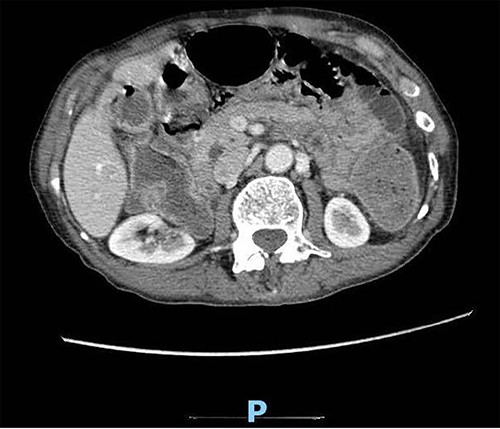

Upon clinical examination, the patient was vitally stable. Abdominal examination revealed a distended abdomen with generalized tenderness. Digital rectal examination revealed an empty rectum with no palpable masses. Laboratory investigations were unremarkable (Table 1). Abdominal X-ray was done (Fig. 2) and showed dilated large bowel loops suggestive of bowel obstruction. Enhanced CT scan of the abdomen and pelvis was obtained (Figs 3–5) and showed a dilated large bowel loop, with air fluid level. A 2.5-cm gallstone was noted, impacting the sigmoid colon and causing partial large bowel obstruction. There was evidence of pneumobilia with air foci within the gallbladder with a suspected fistula with the hepatic flexure.

Enhanced CT scan of the abdomen showing evidence of partial large bowel with pneumobilia, gallbladder seen with interrupted wall and suspected fistula with the hepatic flexure (axial view).